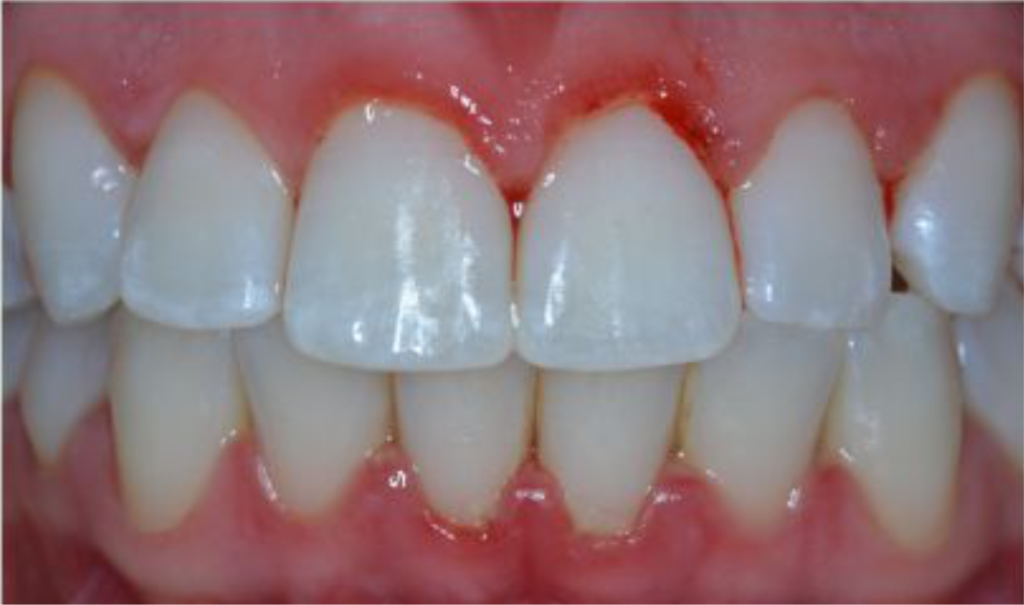

A Periodontite, também conhecida com Doença Periodontal, é a evolução da Gengivite. Com o aumento do acúmulo de Tártaro, que ocorre em direção à raiz, nosso organismo responde às agressões geradas pelas bactérias que o compõem promovendo uma reabsorção do Osso Alveolar, que é de suma importância para a manutenção do dente. Essa Perda Óssea pode se desenvolver de várias formas: localizada, acometendo um ou poucos dentes, ou generalizada, onde praticamente todos os dentes são afetados; pode ter uma evolução lenta, Periodontite do Adulto, ou evoluir de forma rápida e agressiva, onde uma pessoa jovem apresente uma perda óssea em estágio avançado.

Gengiva inflamada;

Vermelha (escura);

Inchada;

Sangramento e Supuração ao toque

Há Perda Óssea e de Inserção

MAU HÁLITO

Migração e mobilidade Dentária

Profundidade de Sondagem aumentada

O Exame Radiográfico evidencia Perda Óssea